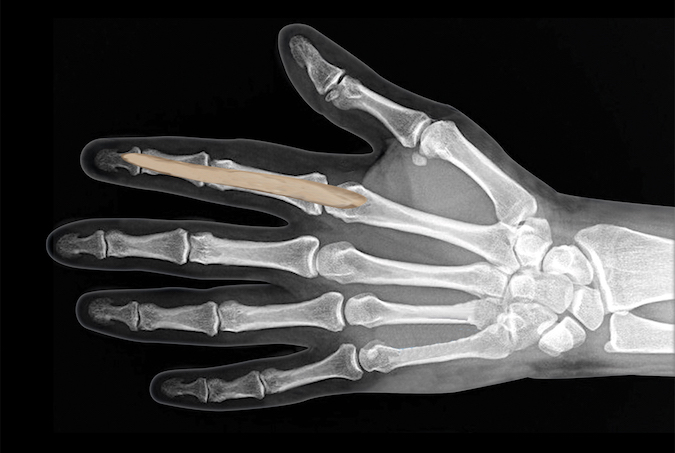

- The absence of bowstringing of the flexors during resisted flexion demonstrates the functional integrity the flexor sheath and its annular pulley system. The fingers have has five annular pulleys and three thinner more flexible cruciate pulleys.

- The annular pulleys provide the fibrous component of the flexor tendon’s fibro-osseous tunnel.

- When a trigger finger is surgically released, the A-1 pulley in section 7 is cut longitudinally.

- During trigger finger release only the A1 pulley should be released in order to avoid bowstring of the flexor tendons.